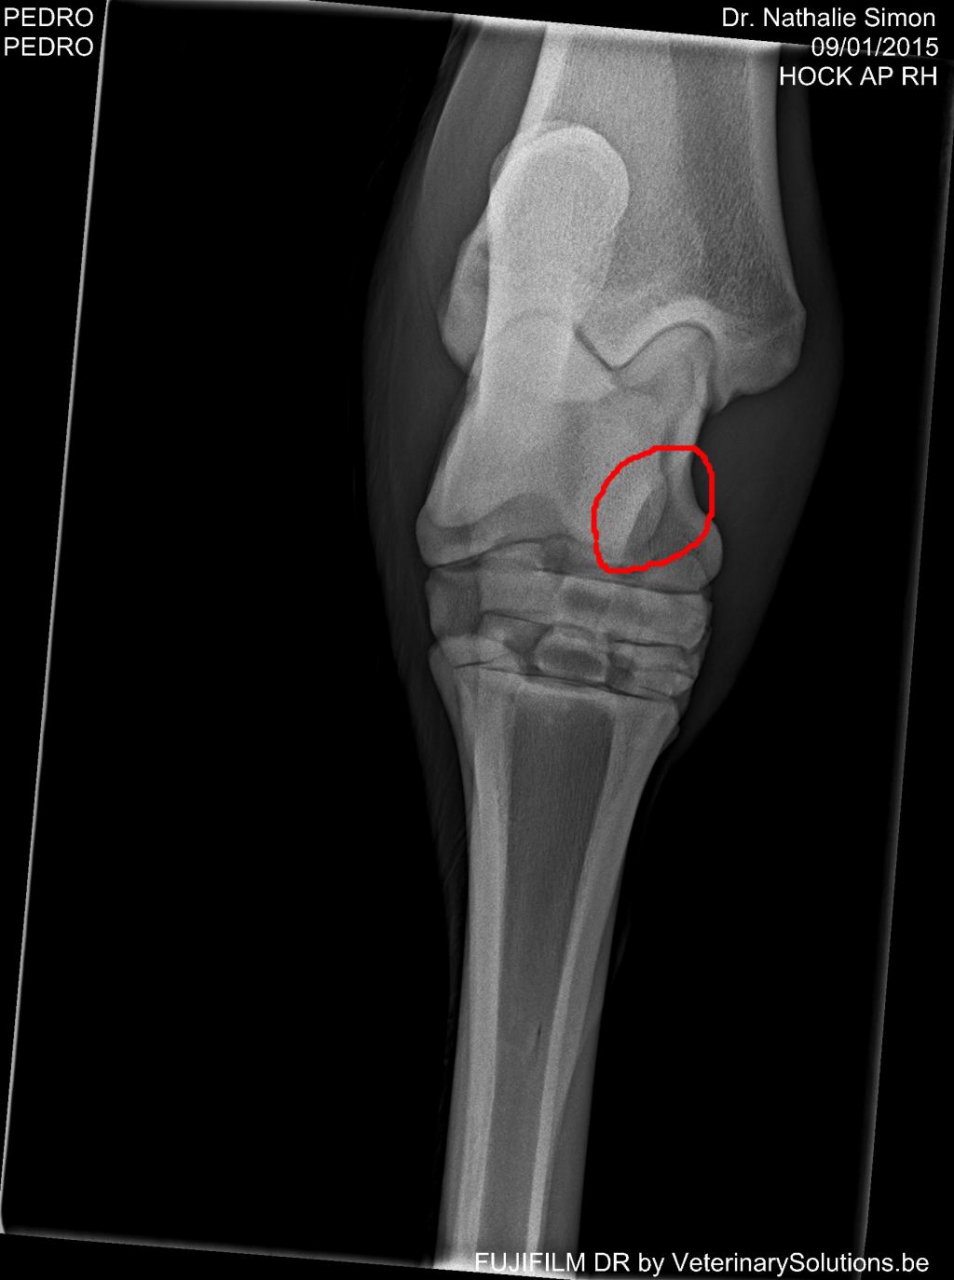

DéconnectéDire merci | Bonjour ha c'est vraiment gentil pour la jument, en tout cas vous êtes quelqu'un de fort psychologiquement car moi j'ai déjà du mal alors qu'il n'a qu'une petite fissure :/ en tout cas merci pour le partage de votre expérience mais pouvez-vous me dire on se trouve la fracture de votre jument ? moi elle se trouve là (entourée en rouge ) |

DéconnectéDire merci | ![]() |